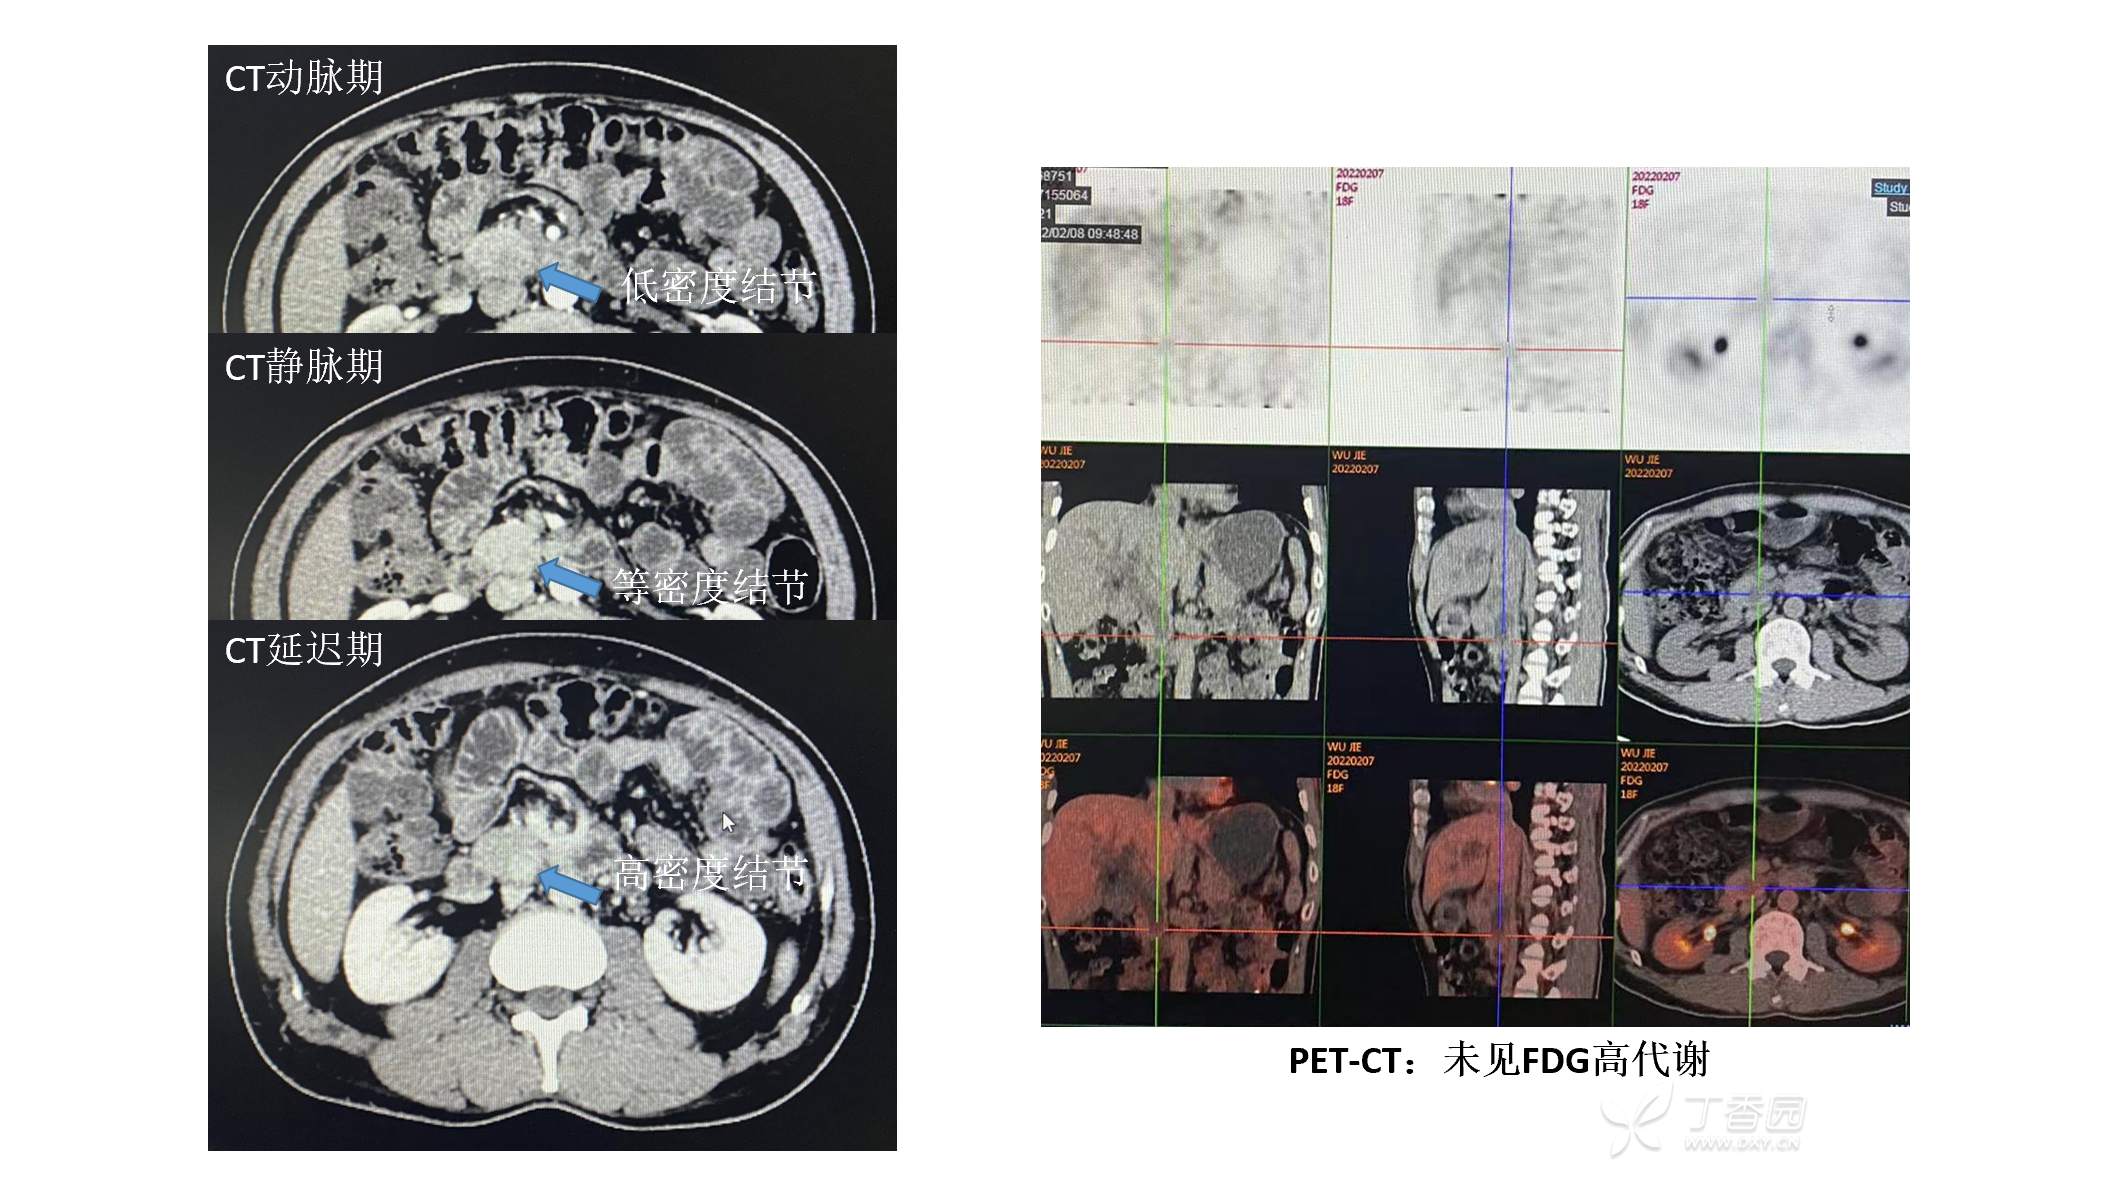

这一例术前CT评估是胰头钩突肿瘤(癌?),但是PET-CT没有高代谢,超声内镜评估是胆总管末端占位。

特殊之处在于增强CT动脉期是低密度占位,静脉期等密度,而延迟期是高密度。

最终病理还是PDAC(CT等高密度的PDAC,不属于乏血供PDAC)。